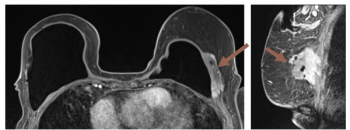

FIRMM-pix, a brain magnetic resonance imaging (MRI) software module recently launched at the International Society for Magnetic Resonance in Medicine (ISMRM) conference, reportedly employs visual biofeedback and gamification that coaches patients to stay still during brain MRI exams.